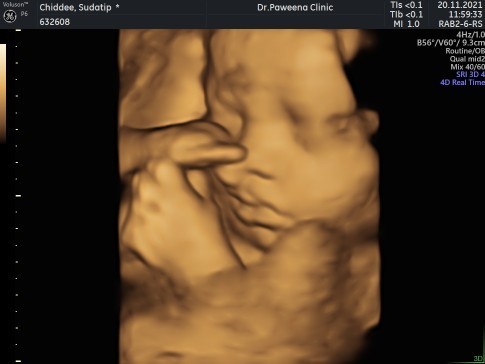

กุมภาเหมือนกันคะ ต้าวแฝด ของเรา